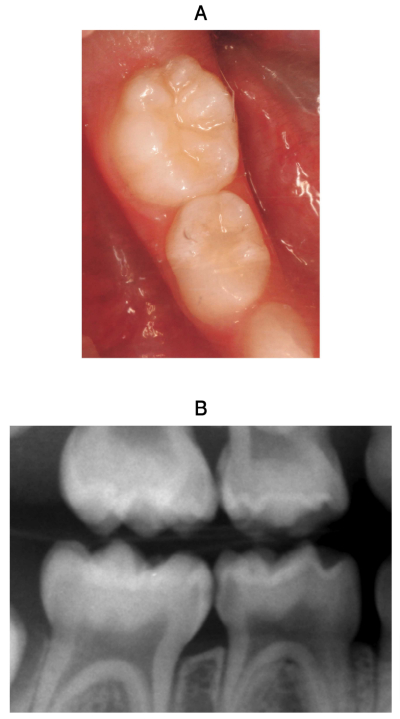

4歳の女児。下顎右側第一乳臼歯の咬合時の違和感を主訴として来院した。冷刺激に一過性に反応するが、自発痛は認められない。歯髄電気診で生活反応を示した。初診時の口腔内写真とエックス線写真を示す。

適切な対応はどれか。1つ選べ。